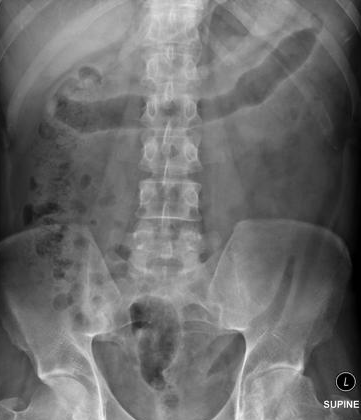

What is this abdominal x-ray showing?

What is being shown on this abdominal x-ray?